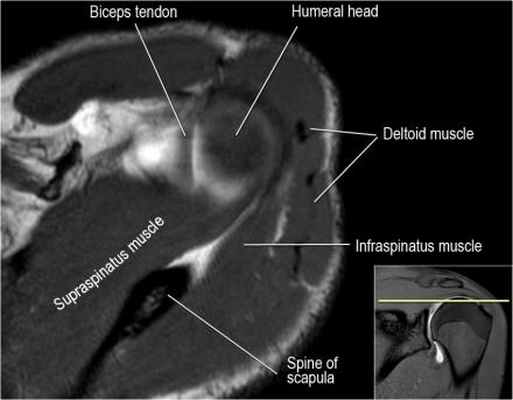

Нормальная анатомия плечевого сустава в аксиальных изображениях и контрольный список.

- поищите os acromiale, акромиальную кость (добавочная кость, расположенная у акромиона)

- обратите внимание что ход сухожилия надостной мышцы параллелен оси мышцы (это не всегда так)

- обратите внимание что ход сухожилия длинной головки двуглавой мышцы в области прикрепления направлен на 12 часов. Область прикрепления может быть различной ширины.

- обратите внимание на верхние отделы суставной губы и прикрепление верхней плече-лопаточной связки. На данном уровне ищется SLAP-повреждение (Superior Labrum Anterior to Posterior) и варианты строения в виде отверстия под сутавной губой (sublabral foramen - подгубное отверстие). На этом же уровне по задне-боковой поверхности головки плечевой кости визуализируются повреждение Хилл-Сакса.

- волокна сухожилия подлопаточной мышцы, создавая бицепитальную борозду, удерживают сухожилие длинной головки двуглавой мышцы. Изучите хрящи.

- уровень средней плече-лопаточной связки и передних отделов суставной губы. Поищите комплекс Буффорда. Изучите хрящи.

- вогнутость заднебокового края головки плечевой кости не следует путать с повреждением Хилл-Сакса, поскольку это нормальная форма для данного уровня. Повреждение Хилл-Сакса визуализируется только на уровне клювовидного отростка. В предних отделах мы сейчас на урвоне 3-6 часов. Здесь визуализируются повреждение Банкарта и его варианты.

- обратите внимание на волокна нижней плече-лопаточной связки. На данном уровне так же ищется повреждение Банкарта.